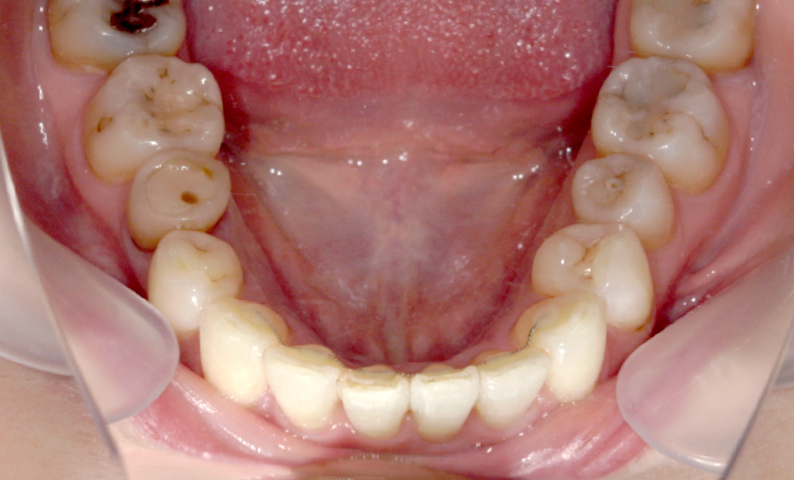

症例_003 下顎だけの部分矯正

治療期間:10ヶ月金額:24万円+税女性前歯のガタガタ下の前歯だけ上顎は補綴治療中

| Before | After |